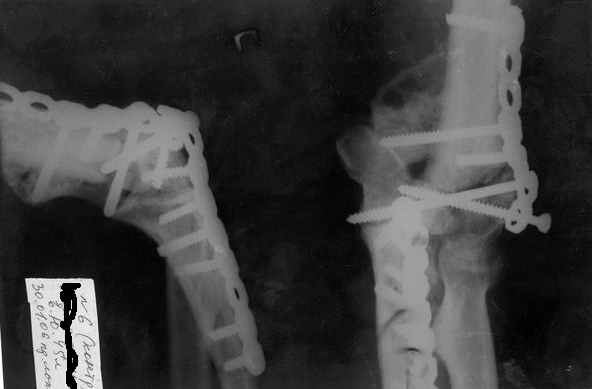

Здравствуйте, коллеги.Мужчина, 45 лет, ДТП 24.10.05. На сегодня неврологических расстройств правой кисти нет, отека нет, движения в правом плечевом и в правой кисти в полном объеме. Правый локтевой сустав сгибани 110*, разгибание 140*, наружняя ротация предплечья 45*, внутренняя 45*. Укорочение правого плеча 4 см. Больной просит у меня совет, стоит ли ему стремиться к эдопротезированию локтевого сустава.Я, к сожелению, не видел ни одного больного после эндопротезирования локтевого сустава.-- С уважением,Анатолий Борзунов

Имея небольшой опыт эндопротезирования локтевого сустава (3 операции - 2 эндопротеза типа Сиваша, и 1 - RM), считаю, что основным показанием к эндопротезированию этого капризного сустава является его гипермобильность (в результате перелома с формрованием разболтанного ложного сустава см. форум от 06.04 2006), или выраженный болевой синдром в сочетании с тугоподвижностью (что встречается у наших больных с гемофилической артропатией). Собственные результаты в целом неплохие - отсутствие болей и гипермобильности, однако, имеется некоторое ограничение разгибания. Сама

операция сопровождается мобилизацией локтевого нерва, а в условиях нарушенной анатомии сросшегося оскольчатого перелома имеется высокая вероятность его травматизации во время выделения, с вытекающими проблемами.

100%-эндопротезирование полужестким имплантатом типа Coonrad-Morrey(Zimmer),GSBIII (Sulzer) или АРЕТЕ(питерская фирма).

Для данного пациента может потребоваться изготовление индивидуального протеза с длинной ножкой.